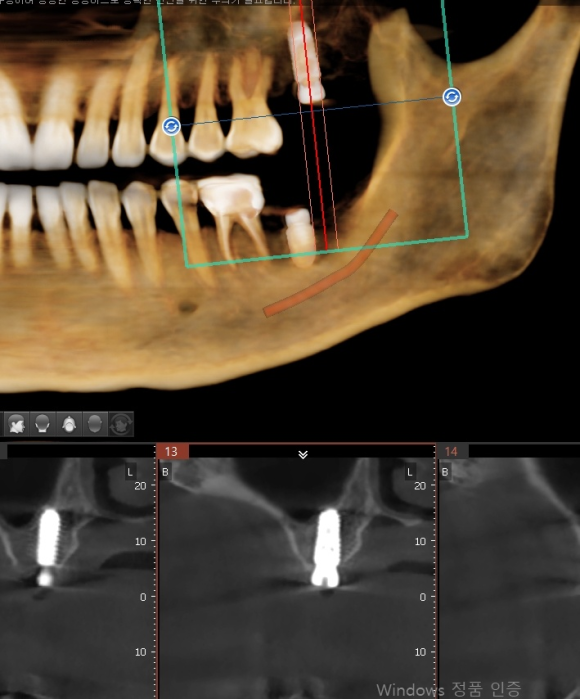

인천에서 오신 분 내과 당일 협진으로 전신 질환 (당요 등등) 확인 후 임플란트 식립.

뼈가 좋지 않아서 충분하게 분석 후 신경 손상을 피하기 위해 전략적이로 보수적으로 접근.

수술 후 3D 사진을 이용한 확인 완료.